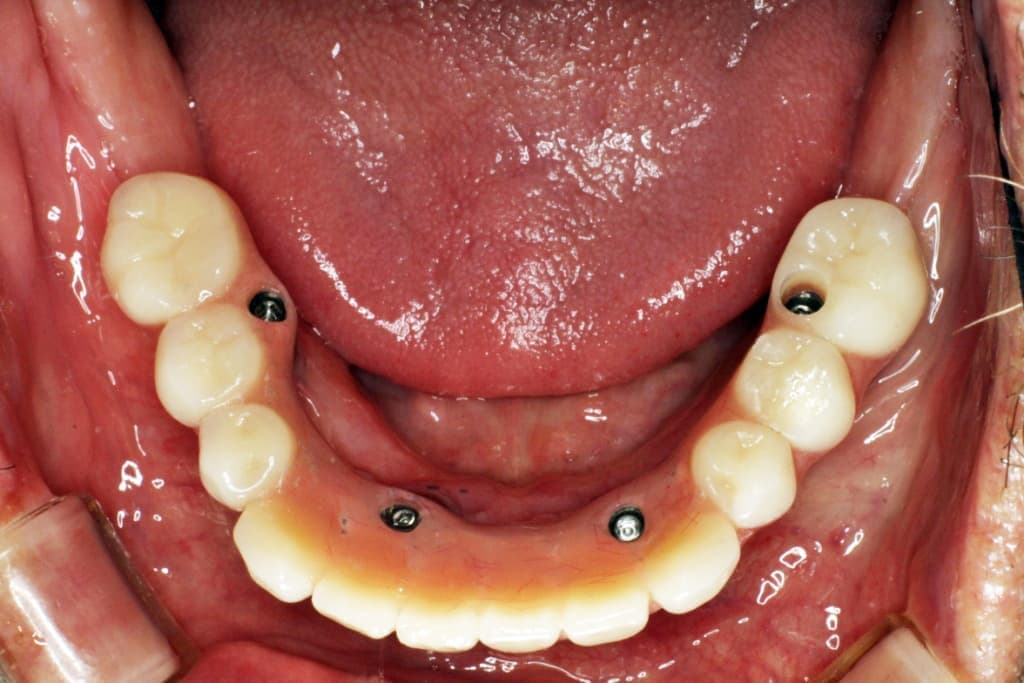

オールオン4は、奥のインプラントを骨のある部分へ斜めに埋め込み力を広く均等に分配することにより、最小4本のインプラントで全ての人工歯を支えることができる術式です。

手術による身体的負担や費用の負担なども最小限に抑えることができます。

※上顎の場合は4本で支えきれない事があり、インプラントの本数追加が必要な場合もあります。

※顎の骨の状態によっては下顎であってもインプラントの本数追加が必要な場合もあります。

被せ物はチタンフレームに組んだジルコニアを使用いたします。